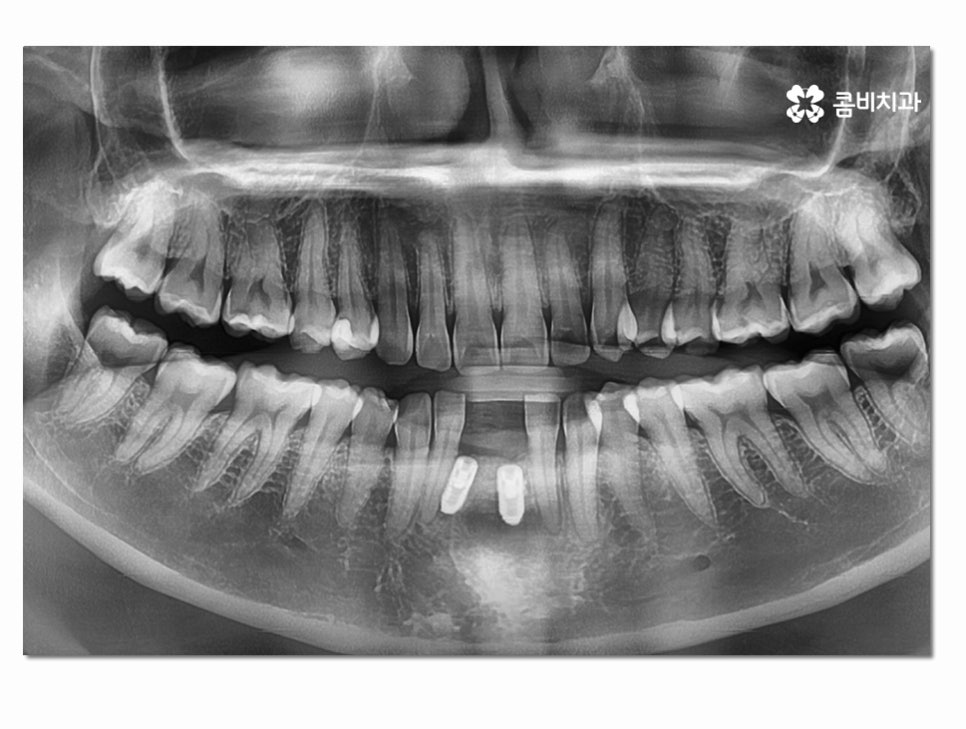

발치 후 임시치아를 부착하였고 염증이 없어진 뒤에

5~6개월 잇몸 뼈가 차오르는 걸 기다렸는데 이 기간은

앞서 설명드린 인공치근을 잇몸 뼈에 튼튼하게 식립하기

위한 회복 기간이라 할 수 있어요.

아랫니 임플란트의 시술 과정과 방법은 사람에 따라 달라질 수 있는데

치아를 잃게 된 원인과 잇몸의 상태, 회복력에 따라서 치료 계획이

달라지며 위 환자분의 경우에는 잇몸질환으로 인하여 치아를

상실했기 때문에 치아 발치 후 잇몸의 회복까지 약 5~6개월의

시간이 소요된 것이라고 할 수 있는데요.

잇몸에 염증이 제대로 사라지지 않은 상태에서는

함부로 임플란트를 식립할 수 없으며

보통 잇몸질환이 심해져서 발치를 하게 되면

잇몸 뼈의 부족으로 인해 뼈이식을 해야 하거나 잇몸 뼈가

차오르는 시간을 충분히 가져야 할 수 있는데요.